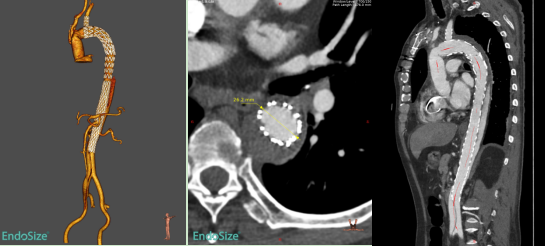

本次入组患者为60岁男性,1个多月前因急性Stanford A型主动脉夹层在我院接受“主动脉瓣交界悬吊+升主动脉及全弓置换+降主动脉象鼻支架置入+三尖瓣成形术”。术后1个月复查CTA提示:象鼻支架以远残余夹层,且夹层累及胸降主动脉、腹主动脉、右侧髂总及髂外动脉,真腔狭窄,假腔大,胸腹主动脉多发夹层破口,胸段肋间动脉以假腔供血为主。

术前CTA